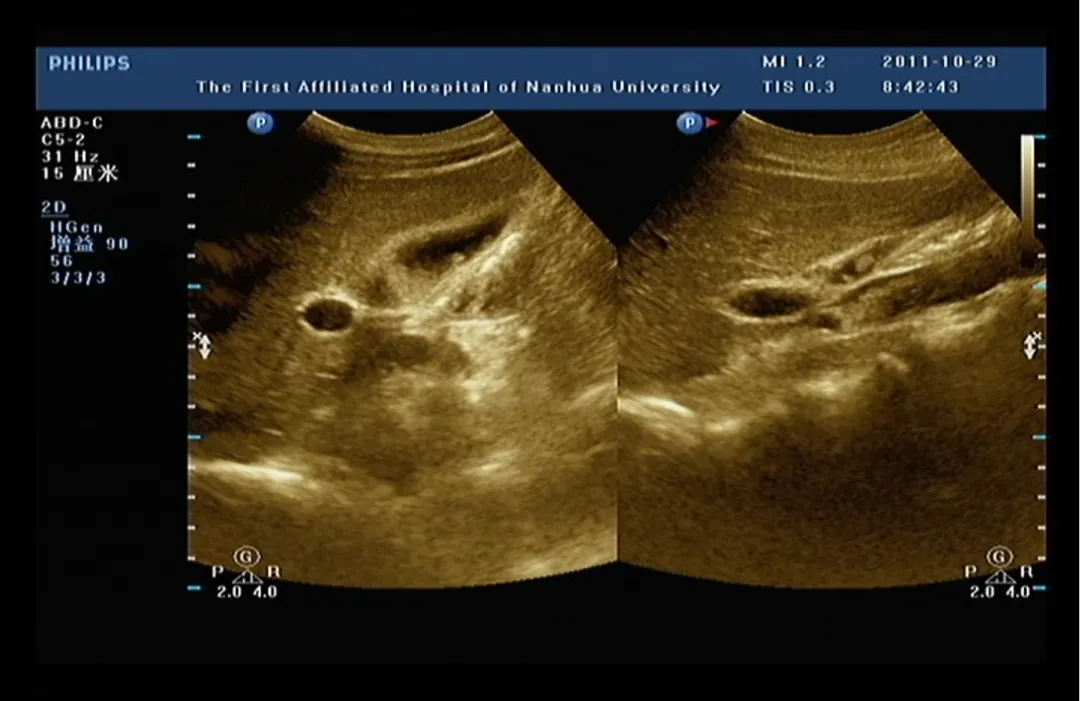

胆囊位于胆囊窝内

纵切面呈梨形

横切面呈圆形或椭圆形

长径50~80mm, 横径30~40mm,胆囊壁厚度不超过3mm,多数小于2mm。

1:胆囊颈;2:胆囊体;3:胆囊底;4:胆囊皱褶

探头置于右肋缘下,大致与肋弓垂直,左右侧动探头,显示较完整的胆囊长轴断面,测量胆囊的长径和横径。

正常值:长径<10cm,横径<3.5cm